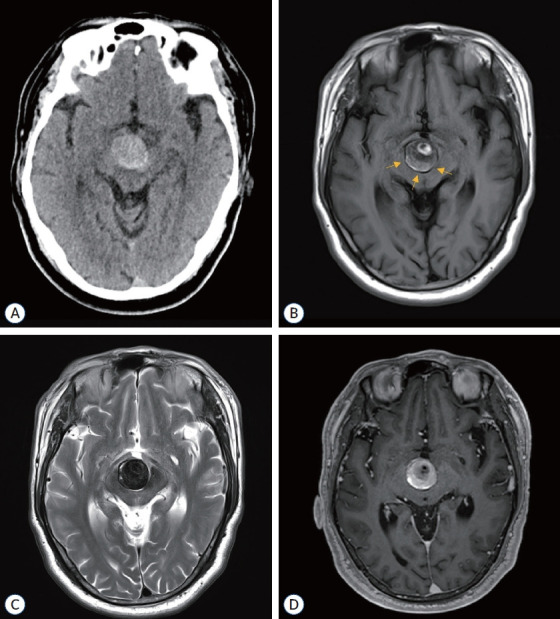

由于巨型部分血栓形成的颅内动脉瘤的自然病史并不乐观,而且缺乏标准化的治疗方法,因此治疗这类动脉瘤面临着巨大的挑战。传统的治疗方法,无论是开放手术还是血管内治疗,往往难以有效控制这些动脉瘤,导致高复发率或严重的发病率。患者是一名 62 岁的男性,基底动脉顶端有一个无症状的部分血栓形成的巨大动脉瘤,表现为左侧偏瘫和构音障碍。诊断成像显示该动脉瘤为巨型动脉瘤,宽颈、管状部分。为了最大限度地保障患者安全,患者接受了两阶段血管内治疗,包括球囊闭塞试验(BOT)和术中监测(IOM)。治疗采用了支架辅助编织内桥(WEB)栓塞和连续双侧椎动脉夹闭。手术成功分离了动脉瘤,术后成像证实没有再堵塞,保留了完整的后循环。患者在 12 个月的随访期间恢复稳定,未出现神经功能障碍。本技术报告展示了使用 WEB 装置和通过双侧椎动脉夹闭逆转血流治疗巨大的部分血栓动脉瘤的可行性和有效性。

Managing giant partially thrombosed intracranial aneurysms presents significant challenges due to their unfavorable natural history and the lack of standardized treatment approaches. Conventional treatments, whether open surgical or endovascular, often struggle to manage these aneurysms effectively, resulting in high recurrence rates or significant morbidity. The patient was a 62-year-old male with a symptomatic giant partially thrombosed aneurysm at the tip of the basilar artery, presenting with left-sided hemiparesis and dysarthria. Diagnostic imaging revealed a giant aneurysm with a wide-necked, canalized portion. A two-stage endovascular treatment was conducted, involving a balloon occlusion test and intraoperative monitoring for maximum patient safety. The treatment utilized stent-assisted Woven EndoBridge (WEB) embolization and serial bilateral vertebral artery trapping. The procedure successfully isolated the aneurysm and postoperative imaging confirmed the absence of recanalization, preserving the intact posterior circulation. The patient showed stable recovery and no neurological deficits during the 12-month follow-up period. This technical note demonstrates the feasibility and efficacy of strategically integrating intrasaccular flow diversion using a WEB device and flow reversal through bilateral vertebral artery trapping for treating giant partially thrombosed aneurysms.